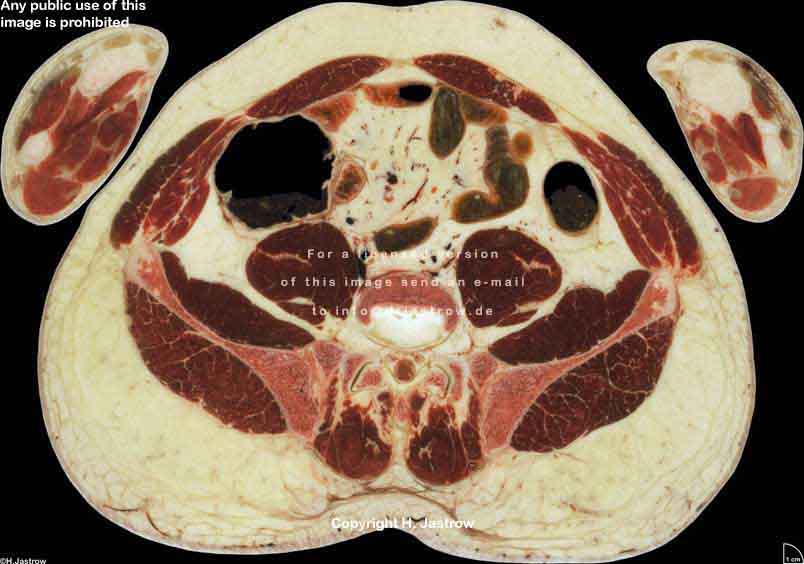

Visible Human male: Sectio transversalis 1763

CT

NMR

Pd                          / T2 \                         T1